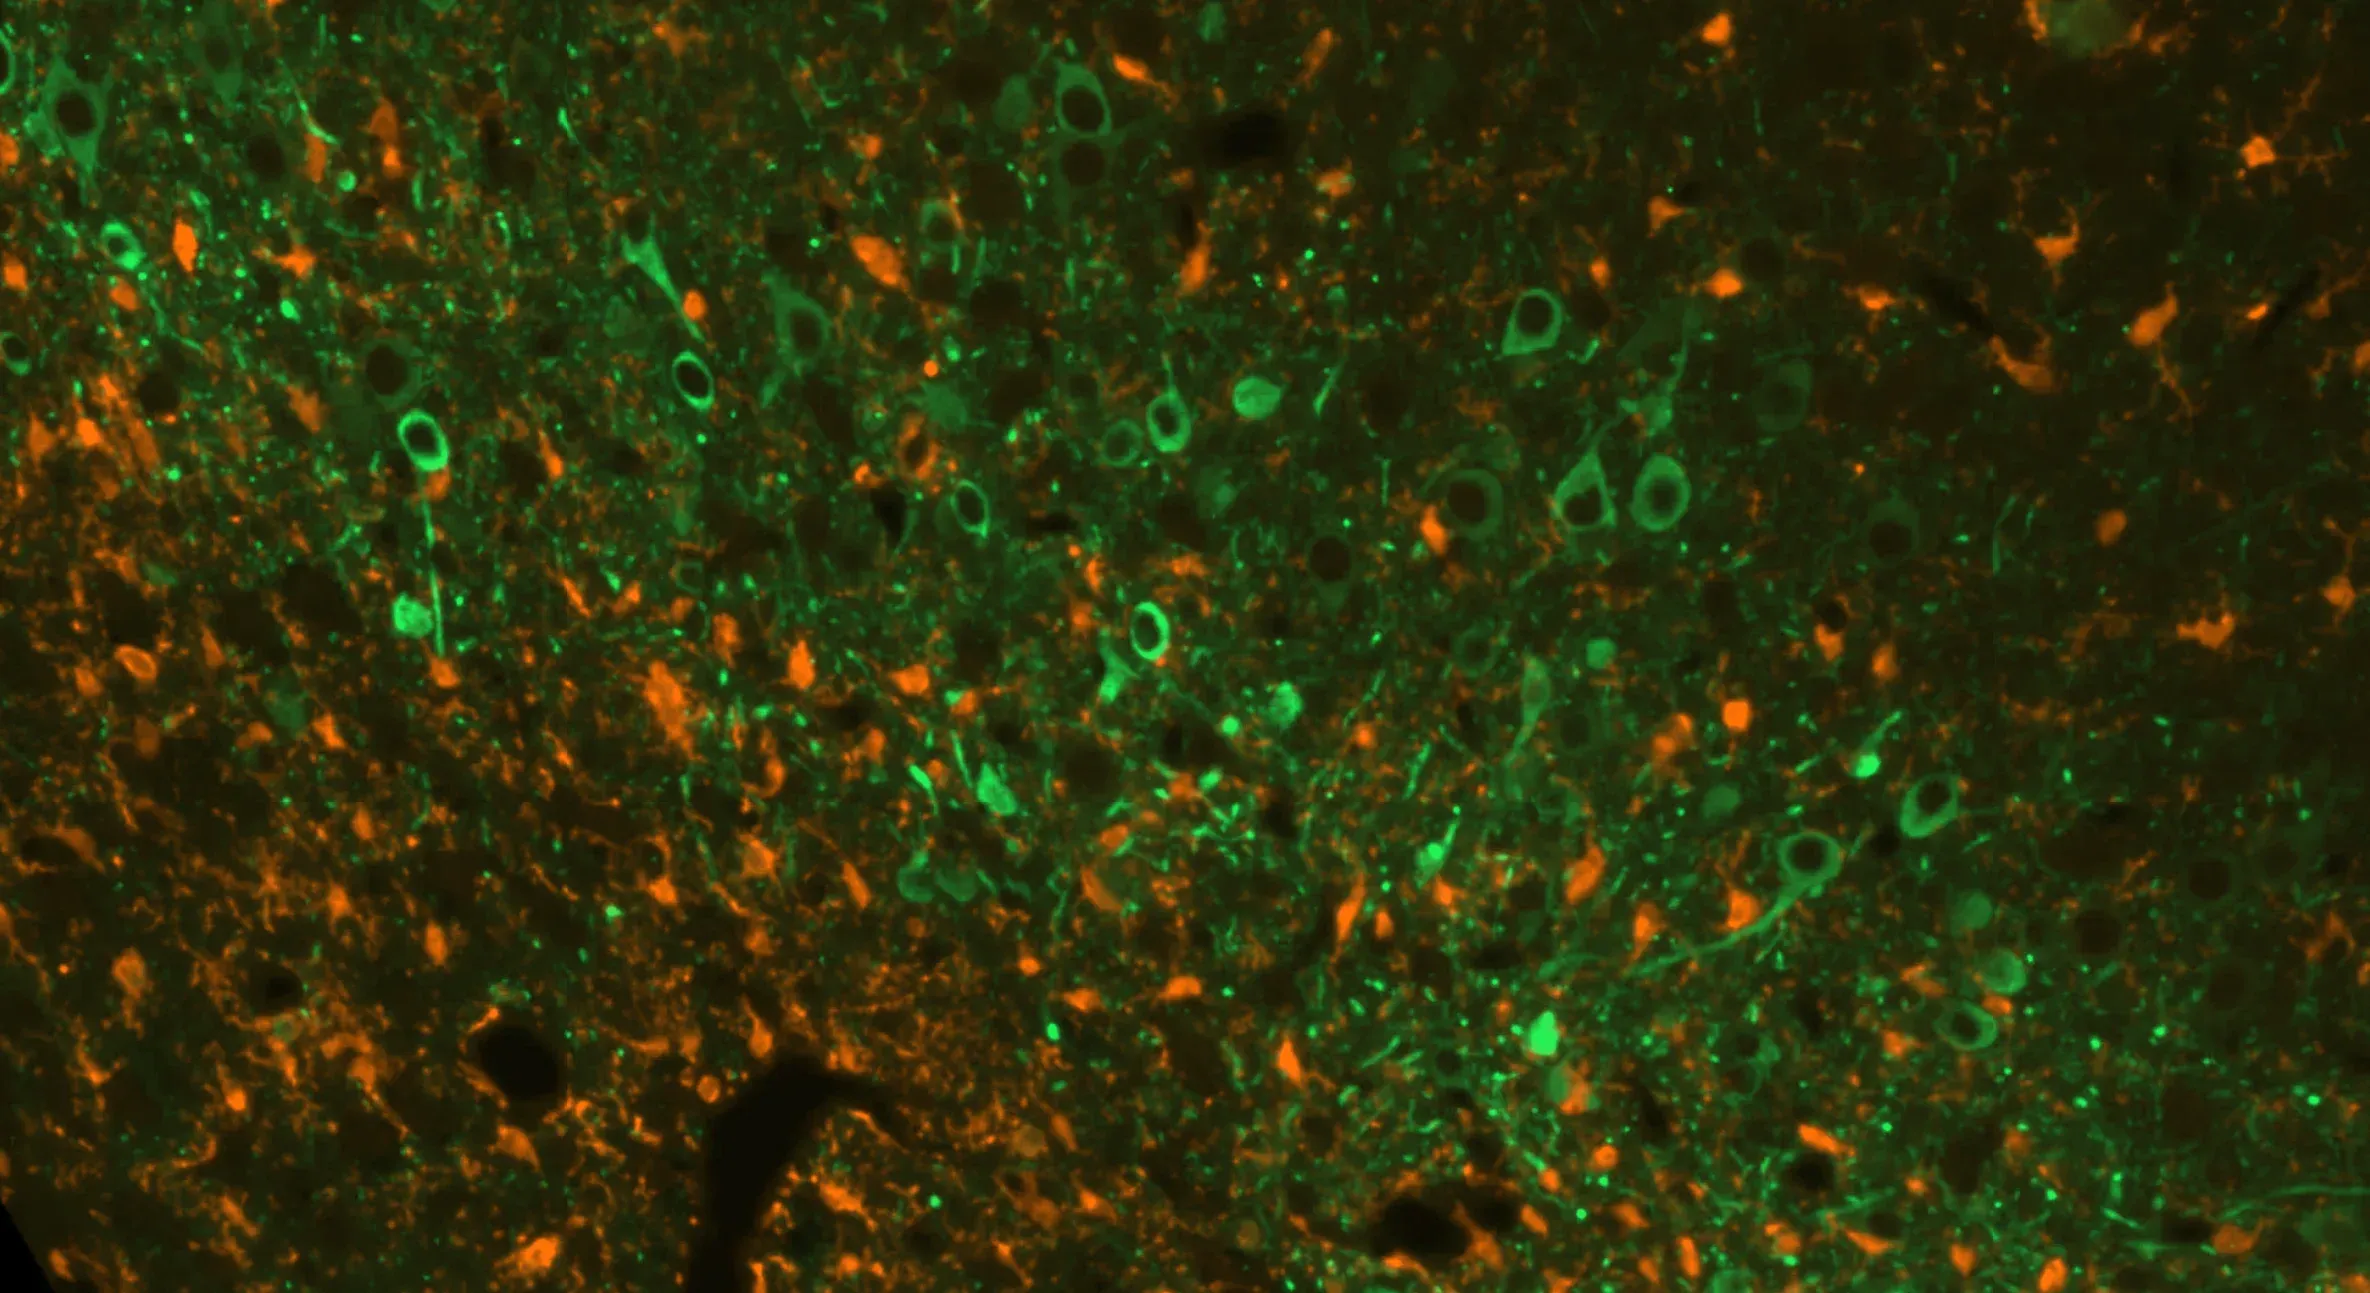

Multiplex immunofluorescence (mIF) image showing tau (green) and microglia (orange) in Biospective's Alzheimer's disease co-pathology model.

The amyloid-β pathology is established using APP/PS1 transgenic mice, which exhibit age-dependent Aβ plaque deposition. To induce tauopathy, adeno-associated virus (AAV) vectors encoding wild-type human tau are delivered via stereotaxic injection into disease-relevant brain regions. This targeted expression leads to the accumulation of phosphorylated tau aggregates within neuronal soma and processes. This co-pathology model demonstrates marked neuroinflammation, neurodegeneration, and associated functional impairments, reflecting complex pathological interactions relevant to Alzheimer's disease.

Neuroinflammatory cells, including activated microglia and reactive astrocytes, are found in close proximity to misfolded amyloid-β and tau (Minter, 2015; Chen and Yu, 2023). In our APP/PS1 mouse model, we have demonstrated a spatial and temporal relationship between Aβ plaques, activated microglia, and non-activated microglia, as well as between Aβ plaques and hypertrophic & non-hypertrophic astrocytes. We also observe a strong microgliosis and astrogliosis in relation to phosphorylated tau in our APP/PS1/hTau co-pathology model.